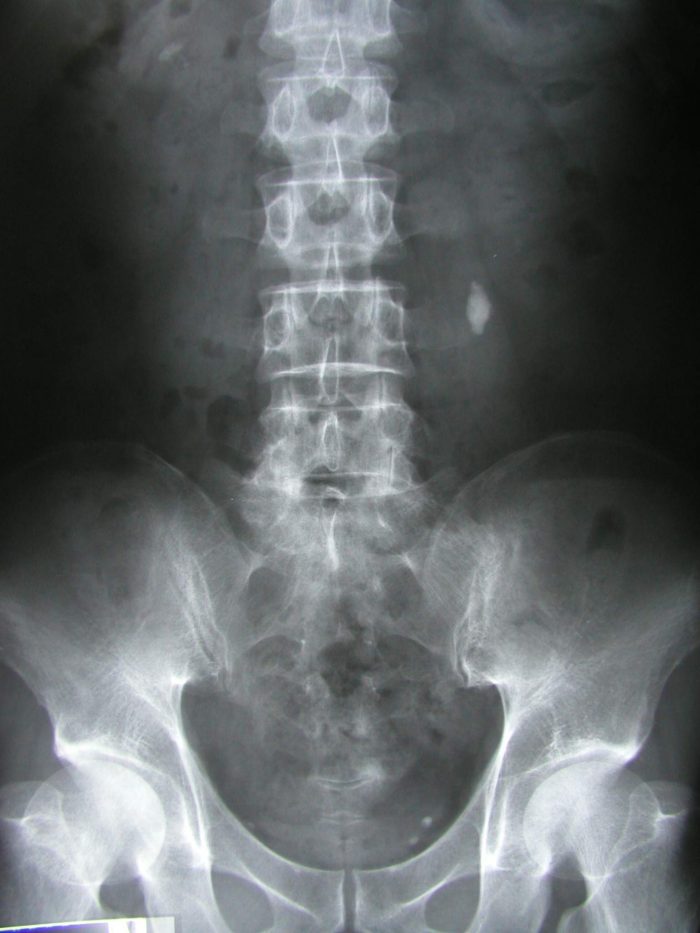

Abdominal X-ray

The x-ray can show the areas of the abdomen on a film. Your doctor may have it on the computer. So, it shows the location of the kidney stones. It is specifically useful in detecting the calcium stones. The radio-opaque nature of the stone makes it easier to detect with x-ray. But, it has radiation risks. Therefore, it is not ideal for pregnant women.